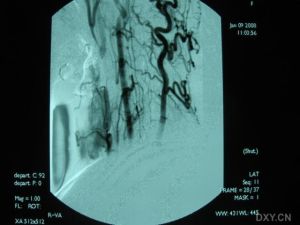

3.腦血管造影有一定的診斷價值71%以上的患者有典型的血管多灶性損害的表現,血管粗細不均,可呈節段性的狹窄或擴張血管阻塞及血管排空延遲等似“臘腸”樣改變,提示腦部血管炎的存在但不能明確是本病的血管炎其他的腦部繼發性血管炎也可有類似的表現有些可因受累的血管太小,腦血管造影可正常

除中樞神經系統症狀外可有發熱、體重下降等全身表現。腦脊液檢查可有細胞數及蛋白的升高,寡克隆區帶陽性。腦活檢可見肉芽腫樣血管炎和/或壞死性血管炎的表現。血管造影可見大腦中小動脈節段性狹窄、擴張及串珠樣改變。1988年Calabrese和Mallek提出了PACNS的診斷標準:①病史和臨床檢查發現原因不明的後天獲得性神經系統損害。②腦血管造影或腦活檢發現有典型血管炎表現。③除外系統性血管炎及其他能引起繼發性中樞神經系統血管炎(血管異常及組織學改變)的各種情況。本例基本皆符合此三條標準。